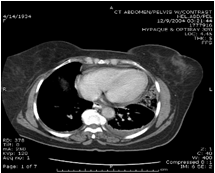

45 yo presents with LUQ pain